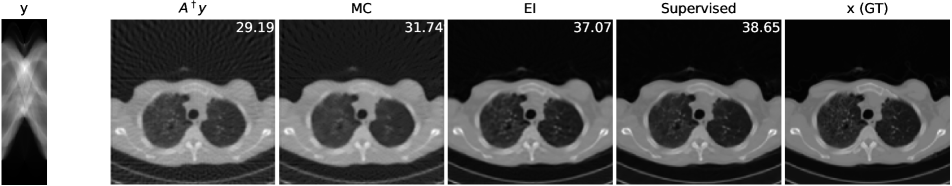

The imaging physics model of X-ray computed tomography (CT) is the discrete radon transform. The physics model is the radon transformation where 50 views (angles) are uniformly subsampled to generate the sparse-view sinograms (observations) . The Filtered back projection (FBP) function, i.e. iradon, is used to approximate . In this task, we exploit the invariance of the CT images to rotations222It is worth noting that shift invariance is not useful for the CT case, as the forward operator is shift invariant itself (see Corollary 1)., and is the group of rotations by degree (=360). We use the CT100 dataset [33], a public real CT clinic dataset which comprises 100 real in-vivo CT images collected from the cancer imaging archive333https://wiki.cancerimagingarchive.net/display/Public/TCGA-LUAD which consist of the middle slice of CT images taken from 69 different patients. The CT images are resized to pixels and we then apply the radon function on them to generate the -views sinograms. We used the first 90 sinograms for training while the remaining 10 sinograms for testing. Note in this task, the supervised trained residual U-Net is just the FBPConvNet proposed in [12] which has been demonstrated to be very effective in supervised learning for sparse-view CT image reconstruction. We train our model with equivariance strength (see SM for more results and the equivariance strength effect). using the sinograms alone while the FBPConvNet is trained with the ground truth pairs .

A qualitative comparison is presented in Figure 4. The sparse-view FBP contains the line artifacts. Both the FBPConvNet and our methods significantly reduce these artifacts, giving visually indistinguishable results. Figure 5 shows the value of PSNR of reconstruction on the training measurements and test measurements and we have the following observations: (i) We would naturally expect the network trained with ground truth data to perform the best. However, we note that the equivariant test error is almost as good despite having no access to ground truth images and only learning on the sparse sinogram data. Furthermore the EI solution is about 7 dB better than the FBP, clearly demonstrating the correct learning of the null space component of the image. (ii) We note that there is a significant gap between training and test error for the FBPConvNet, suggesting that the network may be overfitting. We do not observe this in the EI learning. This can be explained by the fact that the EI constrains the network to a much small class of functions (those that are equivariant on the data) and thus can be expected to have better generalization properties.

We also compared the EI with its adversarial extension in (7) and the supervised learning regularized by equivariance objective. The quantitative results are given in table 1 below. First, MC learning obtains a small improvement in performance over FBP which may be attributable to the fact that FBP is only an approximation to . Alternatively it may be due to the inductive bias of the neural network architecture [34]. Second, the adversarial extension provides a slight improvement to EI and similarly the EI regularization helps the vanilla supervised learning obtain a further 0.6 dB improvement. These results suggest that it is indeed possible to learn to reconstruct challenging inverse problems with only access to measurement data.

| FBP | MC | EI | Sup | |||

|---|---|---|---|---|---|---|

| 50-views CT | 30.24 | 31.01 | 36.94 | 36.96 | 38.17 | 38.79 |